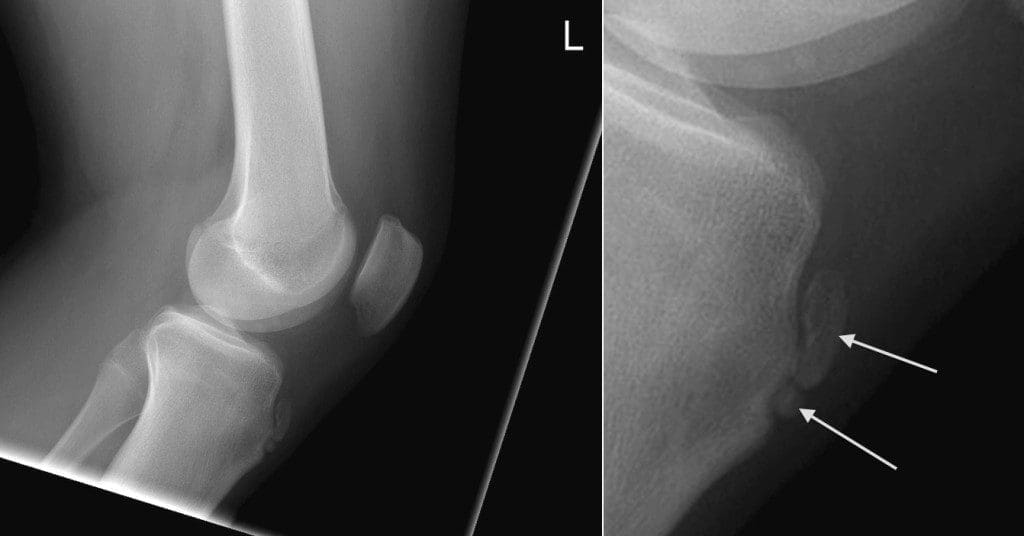

Osgood-Schlatter Disease Diagnosis

Throughout the consultation, the healthcare professional will discuss the children or adolescent’s symptoms regarding their overall health and wellness. They will then conduct a comprehensive evaluation of the knee. This will consist of applying pressure to the tibial tubercle, which should be painful for a patient with Osgood-Schlatter disease. Additionally, the doctor may also ask the child or adolescent to walk, run, jump, or kneel to see whether symptoms are brought on by the movements. Furthermore, the healthcare professional may also order an x-ray of the patienet’s knee to help support their diagnosis or to rule out any other health issues.